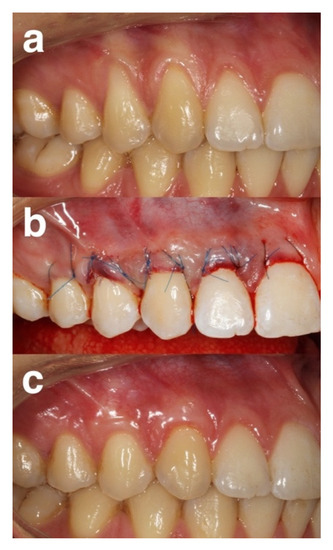

4.5. Surgical Phase